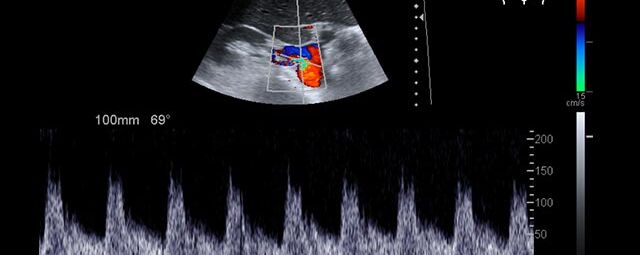

Die Sonographie ist ein bildgebendes Verfahren in der medizinischen Diagnostik, das mit Ultraschallwellen arbeitet. Ultraschall ist Schall mit einer Frequenz oberhalb der menschlichen Hörgrenze. Im medizinischen Bereich werden je nach Körperregion Ultraschallwellen in einem Frequenzbereich von ca. 3,5 – 18 Mhz verwendet. Die körpernahe Ultraschallsonde sendet durch einen piezoelektrischen Effekt kurze Schallwellenimpulse in den Körper. Ultraschall-Gel stellt den Kontakt zwischen Sonde und Körper her. Je nach Gewebeart werden diese Schallwellen im Körper unterschiedlich stark reflektiert. Anhand des zurückgesendeten Schallmusters kann das Ultraschallgerät Schnittbilder berechnen, auf denen die Organe des Körpers nach krankhaften Veränderungen untersucht werden können.

Der Arzt bewegt den Schallkopf mit leichtem Druck in verschiedene Richtungen. Die zu untersuchenden Strukturen können somit aus verschiedenen Perspektiven betrachtet werden. Aussagekräftige Bilder werden festgehalten und digital archiviert, Strukturen oder Organe können zusätzlich vermessen werden. Ein kurzes Befundgespräch erfolgt direkt nach der Untersuchung. Ihr zuweisender Arzt erhält von uns schriftlich einen ausführlichen Befundbericht.